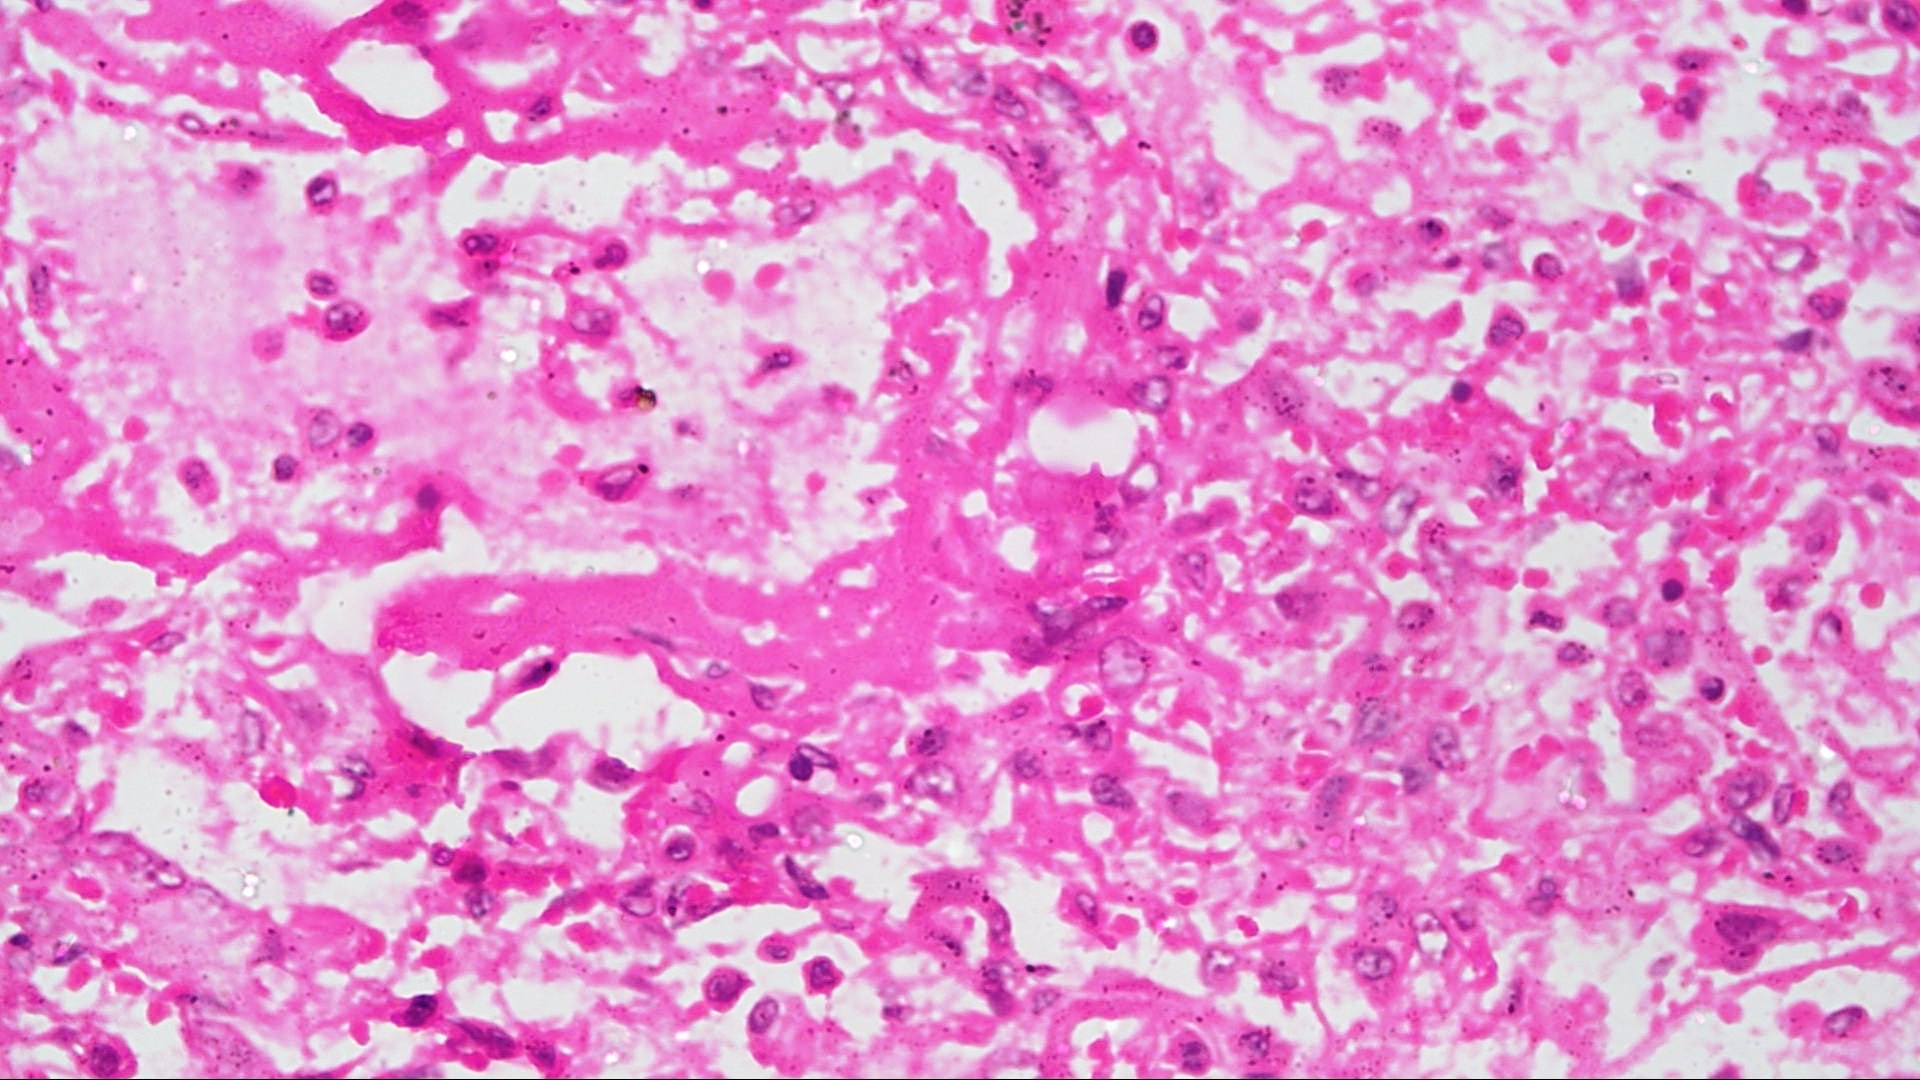

Influenza, also called flu or grippe, an acute viral infection of the upper or lower respiratory tract that is marked by fever, chills, and a generalized . Influenza (flu) is a contagious respiratory illness caused by influenza viruses. Flu is caused by a virus and it can be very . Influenza, or flu, is a serious respiratory illness. It is characterized by a sudden . Symptoms can include fever, cough, sore throat, runny or stuff nose, . Pathology Outlines - Influenza pneumonia Source: i0.wp.com

Influenza, or flu, is a serious respiratory illness. It is easily spread from person to person and can lead to severe complications, even death. Pathology Outlines - Influenza pneumonia Source: i0.wp.com